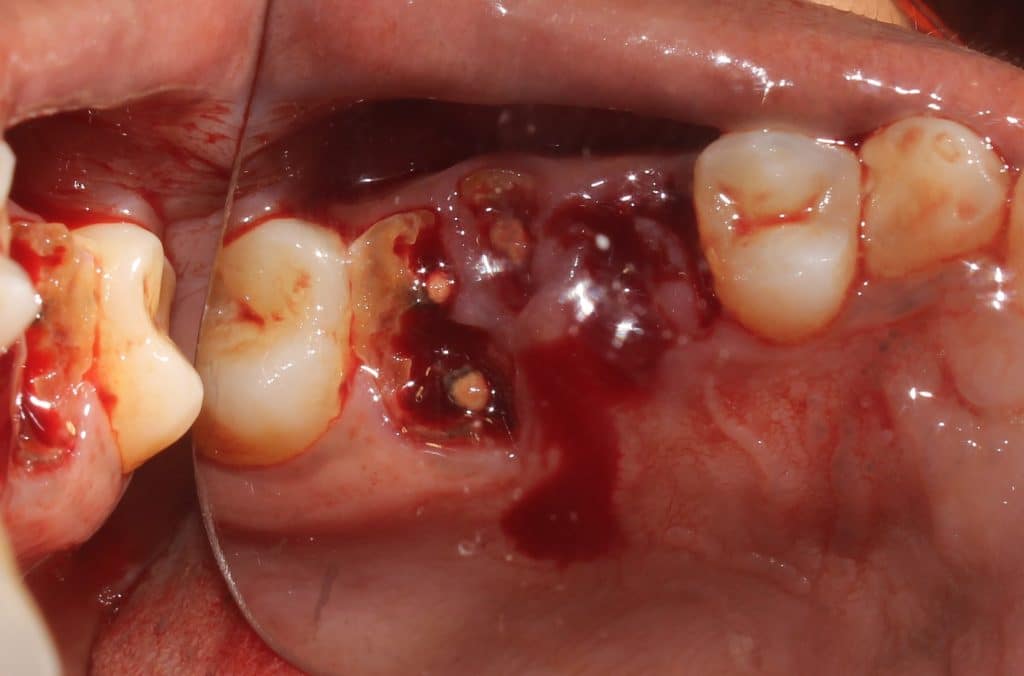

removed root stumps..

collagen sponge and figure of 8 suturing to protect the blood clot..